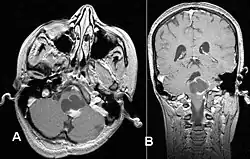

El diagnóstico de este tumor se lleva a cabo normalmente usando la tomografía computarizada (TC) o la resonancia magnética nuclear (RM) del cráneo, con medio de contraste. De manera complementaria, puede añadirse una tomografía por emisión de positrones (PET).[8]

La RM ofrece una mayor sensibilidad en comparación con la TC, si bien no siempre es fácilmente accesible y presenta contraindicaciones, por ejemplo, no se puede utilizar en pacientes con marcapasos, prótesis incompatibles con el campo magnético, clips metálicos, etc. En las imágenes de TC y RM el astrocitoma pilocítico aparece como un tumor con márgenes bien definidos, redondeado, sólido o asociado a macro o microquistes. El 10 % presenta calcificación.[3] La captación de contraste es prácticamente homogénea y muy intensa. Este hallazgo es indicativo de una fuerte vascularización del tumor, aunque en este caso no se considera indicativa de malignidad. En fosa posterior, el diagnóstico diferencial se hace con el meduloblastoma, el ependimoma y el hemangioblastoma, y en la región quiasmática con el craneofaringioma.[9]